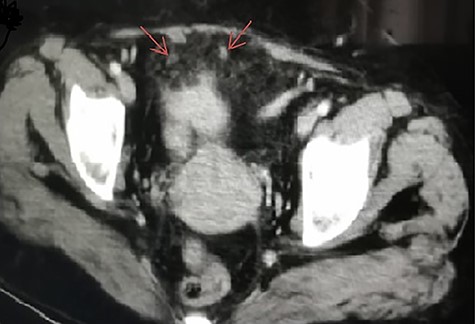

A 42-year-old woman presented to our emergency department with a painful swelling in the suprapubic region persisted for 3 days. She had a history of LC 10 years back at our center for symptomatic gallstones and had no history of comorbidities. The patient had a history of cesarean section twice. She had a pulse rate of 92/min, blood pressure of 110/60 and a temperature of 37.4°C. Physical examination revealed abdominal tenderness in the suprapubic region, right and left lower quadrant, and exhibited signs of peritoneal irritation, muscle guarding and rebound tenderness. Laboratory tests resulted with white blood cell: 15 200/mm3, hemoglobin: 11.9 g/dl, C-reactive protein: 24 mg/dl, and other biochemical parameters were also normal. On oral contrast-enhanced abdominal computed tomography (CT) performed in the emergency room (Fig. 1), the mesenteric adipose planes were inflamed and contaminated. Minimal free fluid was observed in the periphery of the intestinal loop in the pelvic area. At first, it was not stated on tomographic interpretation that there were gallstones in the abdomen. Considering that the patient had signs and symptoms of acute abdomen, she underwent diagnostic laparoscopy. In exploration, it was observed that the small intestines were edematous, the omentum was inflamed in the pelvic region and the omentum was attached to the anterior abdominal wall, bladder and uterus by gato. Since a clear diagnosis could not be made in the patient for etiology, abdomen was opened with a midline incision under the umbilicus. Infected reactive fluid located between the omentum and the anterior abdominal wall and pelvic region was aspirated. Adhesions due to previous cesarean sections were removed. During the adhesiolysis, stones the largest of which was ~2 cm in size, and abscesses were detected in the omental granuloma/cake (Fig. 2a, b). These stones were thought to remain in the abdomen due to the previous LC. Partial omentectomy with abscesses drainage was performed. The abdomen was irrigated and the stones were retrieved. No other pathology was detected in exploration and no additional surgical intervention was performed. The postoperative period was uneventful, and she was discharged on the fourth postoperative day. Spilled cholesterol gallstones were determined to be the cause of the acute abdomen in this case. Histopathological examination confirmed the diagnosis. Written informed consent was obtained from the patient for the anonymized information to be published in this article.

CT scan of abdomen and pelvis axial view showing intra-abdominal gallstones.